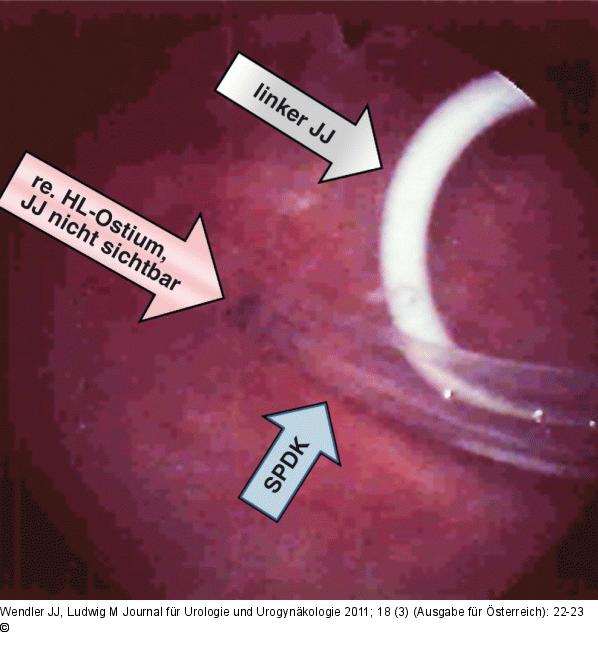

Abbildung 3: JJ-Katheter Fehlplatzierung eines suprapubischen Blasenkatheters (SPDK) im rechten Harnleiter mit Rückschub eines liegenden JJ-Katheters rechts; liegender JJ-Katheter links (rechts im Bild) |

Fehlplatzierung eines suprapubischen Blasenkatheters (SPDK) im rechten Harnleiter mit Rückschub eines liegenden JJ-Katheters rechts; liegender JJ-Katheter links (rechts im Bild) |